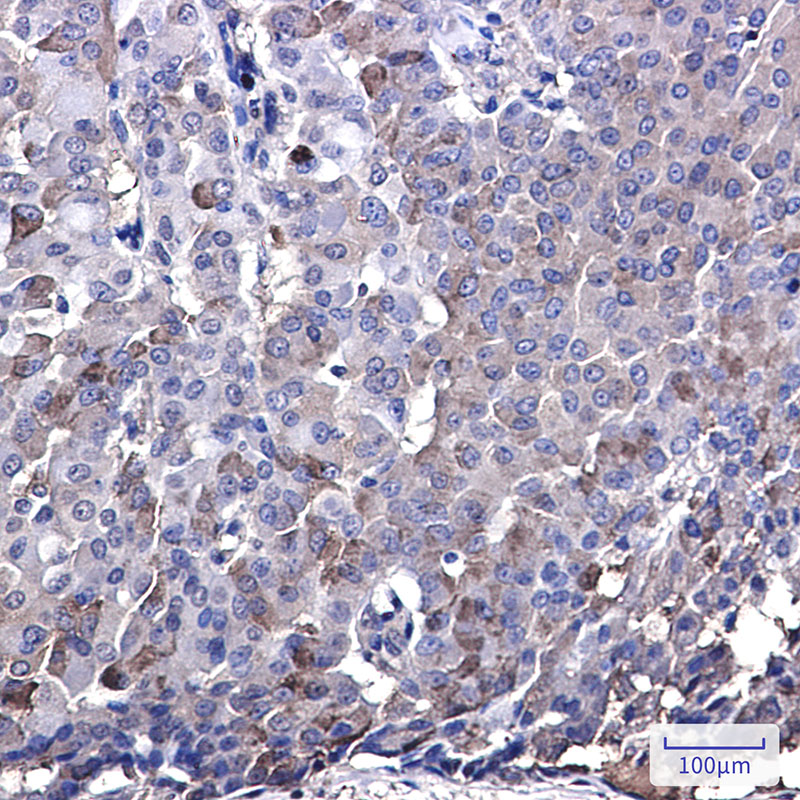

IHC 1/50-1/100 Human,Mouse,Rat

**摘要**:通过Western blot和免疫组化使用IRF7抗体,该研究发现乳腺癌中IRF7低表达与免疫抑制微环境相关,过表达IRF7可激活干扰素通路并抑制肿瘤生长,提示其作为预后标志物的潜力。